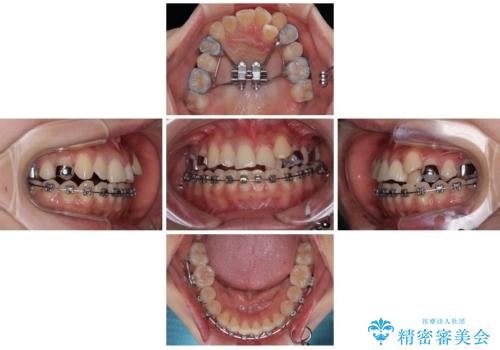

急速拡大装置 狭い上顎歯列を改善して、八重歯を改善した片側抜歯矯正治療

- 左上の前歯のがたつきを主訴に来院された患者様です。

上顎歯列が下顎の歯列に対して狭小であり、一部下顎の奥歯が上顎よりも外側に位置している状態でした。

上顎の歯列を拡大しスペースを設け、さらに左上の小臼歯を一本抜歯し左上の八重歯を歯列内に入れ整えていくことにしました。

MARPEについて

MARPE(Mini screw assisted rapid palatal expansion )は、上顎の幅を広げる矯正治療です。

歯だけでなく、あごの骨に直接力をかけて広げるのが特徴です。

これまで難しかった大人の方でも、上あごの拡大が可能な場合があります。

上顎の骨に小さなネジ(マイクロインプラント)を使用し、装置をしっかり固定します。

その力で上あごの正中(真ん中の骨のつなぎ目)を少しずつ広げていきます。